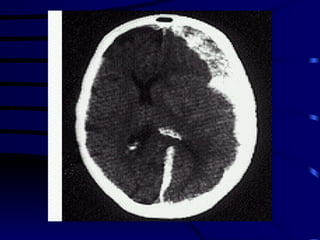

DIAGNOSTICO AIT : clínica, TAC o RMN positiva en el 15 al 30 % de los casos. Ictus establecido:  TAC no es útil en las primeras 24 hs. de una isquemia. RMN: detecta infartos a partir de las primeras 3 hs. TAC : pone en manifiesto el 100% de los hematomas.

DIAGNOSTICO AIT :clínica, TAC o RMN positiva en el 15 al 30 % de los casos. Ictus establecido: TAC no es útil en las primeras 24 hs. de una isquemia. RMN: detecta infartos a partir de las primeras 3 hs. TAC : pone en manifiesto el 100% de los hematomas.